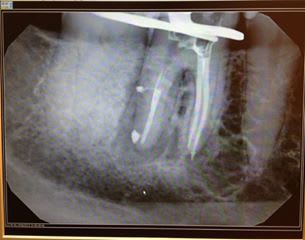

bonjour j ai recupéré un cas j ai posé deux implants 27,28et je doit me servir de ces deux la pour faire un bridge24,28

Problème: le patient m'a dit que c'était du branemark j ai commandé les pièces adéquates avec un conseiller nobel .

Patatras les pilers flottent j ai contacté un responsable NOBEL qui m a dit que c'était pas du Branemark.

Je suis pas (encore) spécialiste Zimmer, mais les trous à l'apex... (Par contre le fut me semble différent). Maintenant, vu que tu parles de Branemark, ce serait des implants à hexagone externe, non ?

j ai fait des recherches c est vrai qu 'il y a un branemark qui ressemble mais cela vouddrait dire que hexagone aurait été detruit ce que la responsable NOBEL m a dit etre impossible

il y aurait un Zimmer mais tout ne concorde pas avec un trou oval quant a celui qui a deux trous ovales il y aurait un IMZ mais celui ci a une surface lisse

Encore une fois, pour identifier un implant, il est nécessaire de connaître le type de connexion : pas le pilier, la connexion (hexagone ext, int, trilobe, créneaux... )

2/ à première vue comme çà, çà colle assez bien avec des zimmer...dont le col est pété...mais j'attends de voir des images plus nettes pour me prononcer...;-)

amha, c'est du tout bon à mettre à la benne...semblerait qu'il ne reste plus que le filetage interne...mais plutôt que les photos, déjà remet les radios comme il faut tel que je te l'ai dit...çà sera bien plus net et çà me permettra d'analyser ces implants dans le détail...